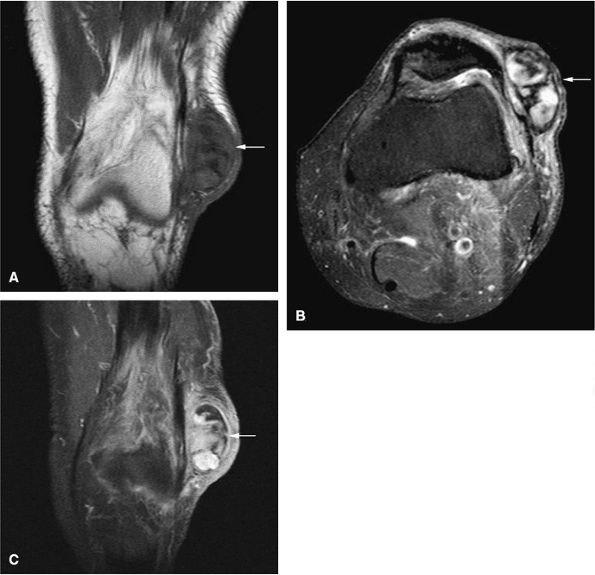

FIGURE 14-64 ● Giant cell tumor. (A) Anteroposterior and (B) lateral radiographs show an osteolytic lesion involving the subchondral bone of the tibial plateau. Cortical thinning and expansion can be seen. (C) Coronal T1-weighted image shows subchondral extension of the tumor (arrow). Tumor contents demonstrate low signal intensity on the coronal (C) and axial (D) T1-weighted images and are hyperintense on the coronal (E) and axial (F) T2-weighted images. Peritumoral edema (arrow) is noted on the axial fat-suppressed T2-weighted fast spin-echo image (F).

Low to intermediate signal intensity on T1-weighted images and high signal intensity on T2-weighted images (Fig. 14-64)92

Heterogeneity in T2-weighted images may represent central areas of liquefaction, hemorrhage, or necrosis (Fig. 14-65).

Aoki et al. reported MR detection of hemosiderin in 63% of giant cell tumors.93 The low-signal-intensity hemosiderin is attributed to extravasated erythrocytes in the tumor and the phagocytic function of the tumor cells. Areas of hemosiderin were most evident on gradient-echo sequences.

Fluid–fluid levels are sometimes seen on MR images.94

Areas of necrosis (i.e., signal inhomogeneity), cortical erosion, and associated effusions may also be identified on MR images.

Intratumoral hemorrhage may produce bright signal intensity on T1- and T2-weighted images, although the tumor generally demonstrates low signal intensity on T1-weighted images and increased signal intensity on T2-weighted images.